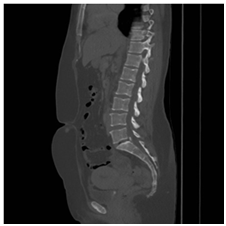

Staging CT chest & abdomen, showed bilateral lung nodules and numerous subcutaneous nodules, the largest seen in the umbilical area (Figure 4). Histology of the right breast biopsy reported staining for Melan-A & HMB45 is positive (Figures 5A‒5D). No staining for Cam5.2, ER, PR, CK7 and CK20. Ki67 is 10%. Appearances and immuno-profile are consistent with metastatic malignant melanoma. Due to disease dissemination, the patient has been referred to palliative oncological treatment.

Figure 4 CT abdomen with a subcutaneous nodule in the umbilical area.